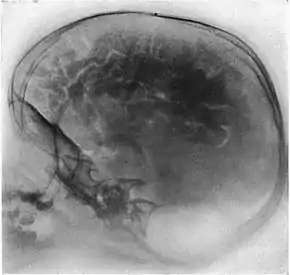

پنوموآنسفالوگرافی (به اختصار PEG ؛ همچنین به عنوان "مطالعه هوا" نیز نامیده می شود) یک روش پزشکی رایج بود که در آن بیشتر مایعات مغزی نخاعی (CSF) با استفاده از یک پونکسیون کمری از اطراف مغز تخلیه و با هوا ، اکسیژن ، یا هلیوم جایگزین می شدند. این عمل باعث می شد ساختار مغز در تصویر اشعه ایکس با وضوح بیشتری نمایش داده شود. این فرایند از ونتیکولوگرافی مشتق شده است. ونتیکولوگرافی روشی ابتدایی و قدیمیست که در آن هوا از طریق سوراخهایی که در جمجمه ایجاد شده، به بدن تزریق می شود.

پنوموآنسفالوگرافی از تصاویر ساده اشعه X استفاده می کند که برای تشخیص بافت های نرم مانند مغز کیفیت چندانی ندارند. علاوه بر این، تمام ساختارهای تصویربرداری شده بدن، روی هم قرار گرفته اند، که این امر امکان بررسی بخش های خاصی از بدن که مورد توجه هستند را دشوار می کند (برخلاف اسکنرهای مدرن که قادر به تولید برش های مجازی از بدن، از جمله بافت های نرم هستند). بنابراین، پنوموآنسفالوگرافی معمولاً ناهنجاری ها و عوامل غیر معمول در بدن را به طور مستقیم تصویر نمی کند، بلکه اثرات ثانویه آنها را نمایش می دهد. ساختار کلی مغز شامل شکاف ها و حفره هایی است که توسط CSF پر می شوند. هم مغز و هم CSF سیگنال های مشابهی را در تصویر اشعه ایکس تولید می کنند. با این حال، تخلیه CSF باعث افزایش کنتراست بین ماده مغز و شکافهای (اکنون تخلیه شده) داخل و اطراف آن می شود که به صورت سایه های تیره بر روی عکس اشعه X نشان داده می شوند. هدف از پنوموآنسفالوگرافی ترسیم این ساختارهای پر از هوای به وجود آورنده سایه است تا بتوان شکل و محل آنها را در بدن تعیین کرد. پس از این مرحله، یک رادیولوژیست باتجربه فیلم های اشعه ایکس را بررسی می کند تا متوجه شود آیا شکل یا محل این ساختارها به دلیل وجود انواع خاصی از ضایعات در بدن، مخدوش شده و تغییر شکل داده است یا خیر. این همچنین بدان معنی است که برای این که ضایعه ای در تصویر قابل مشاهده باشد، ضایعه باید یا در لبه ساختارها واقع شود یا اگر در جای دیگری از مغز قرار دارد، باید به اندازه کافی بزرگ باشد تا بتواند بافت های سالم اطراف را تا حدی تحت فشار قرار داده که باعث ایجاد تغییر در شکل حفره های پر از هوای موجود در فواصل دورتر شوند. (در نتیجه در این روش، تومورهای تشخیص داده شده از فواصل دوتر، احتمالاً تومورهای نسبتاً بزرگی هستند.)